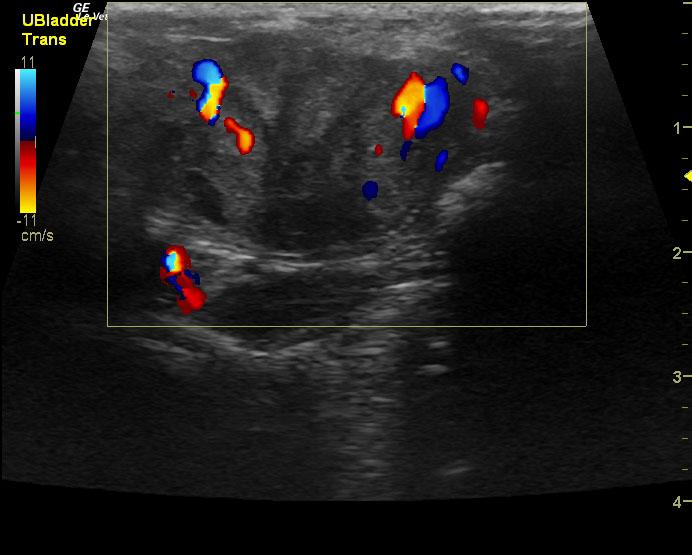

An 18-year-old SF DSH was presented for evaluation of hematuria and stranguria. Urinalysis showed SG of 1.019 and proteinuria. Abnormalities on CBC and serum biochemistry were anemia and azotemia.

An 18-year-old SF DSH was presented for evaluation of hematuria and stranguria. Urinalysis showed SG of 1.019 and proteinuria. Abnormalities on CBC and serum biochemistry were anemia and azotemia.